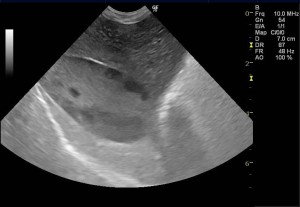

以前より胆嚢内の粘液腫様変性が認められていたため注意して経過観察を実施していた症例です。超音波では、胆嚢の拡張は認められないものの、内部の変性(キウイフルーツ様パターン)は顕著に認められました。

診断:胆嚢粘液嚢腫